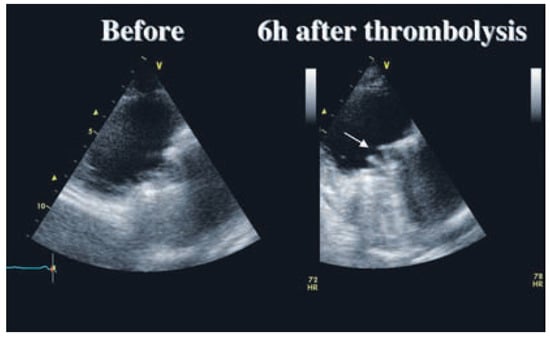

Figure 1. End-diastolic parasternal long axis view of the right ventricle centered on the prosthetic tricuspid valve. Before thrombolysis, there is no visible leaflets movement. After thrombolysis, the two leaflets are opening symmetrically (arrow).

A diagnosis of a subacute thrombosis of the tricuspid St. Jude valve was made and an intravenous thrombolysis was started. We administered a recombinant tissue plasminogen activator (rt-PA; Actilyse®, Boehringer Ingelheim, Germany) with a loading dose of 10 mg IV, followed by 90 mg IV for 90 min. Heparin 5000 U bolus IV was administered 2 hours after the loading dose, followed with 30 000 U/ 24 h IV. One hour after the end of the thrombolysis, the diastolic rumble had disappeared. A transthoracic examination, 6 hours after the beginning of the fibrinolysis, showed a complete excursion of the two leaflets with a mean transprosthetic gradient of 2 mm Hg (Figure 1, Figure 2 and Figure 3).